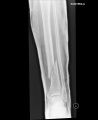

Lýtková a holení kost,10cm nad kotníkem.

Hrůza,ale už normálně jezdím.

v lednu to byly tři roky,prostě podjelo přední kolo a pomalá reakce+zamrzlý kufr a už to bylo.

Bud rad ze 10cm nad kotnikem a ne kotnik. Tohle je pomerne snadno resitelne. Myslim medicinsky.